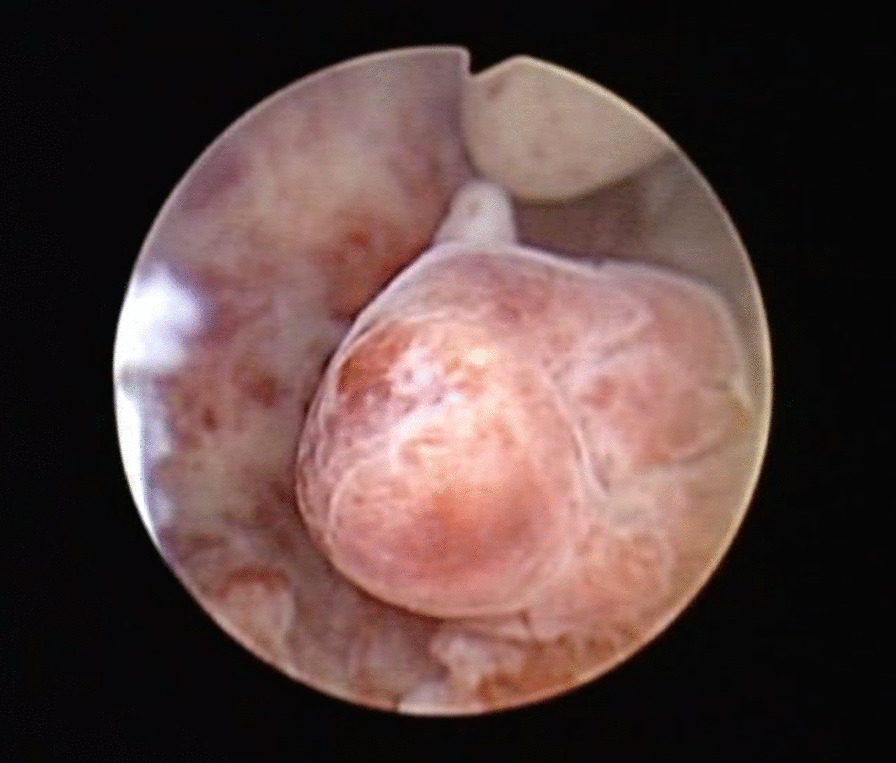

All 44 patients underwent hysteroscopy. A single lesion was found in 40 patients (90.9%), and the mean size was 2.83 ± 0.73 cm (ranging from 0.5 to 6 cm). The specific distribution of the lesions was as follows: 10 cases in the uterine cavity bottom, 8 in the anterior wall, 7 in the left uterine angle, 5 in the right uterine angle, 5 in the posterior wall, 2 in the right anterior wall, 1 in the right wall, 1 in the right anterior wall near the cervical intraoral cavity, and 1 in the left wall. The surfaces of 8 lesions had rich blood vessels, and 2 lesions had atypical vessels, which is a typical hysteroscopic morphology (Fig. 1). In addition, 4 patients had multiple lesions.

Fig. 1.

Atypical polypoid adenomyoma seen on hysteroscopy (lesions located in the posterior wall of the uterine cavity, diameter 2.0 cm, irregular shape)

Among the patients in this group, 40 had single lesions. The diameters of the lesions were 0.5 to 6 cm, with an average diameter of 2.83 ± 0.73 cm, which was consistent with the literature [19]. APA does not have a unique appearance under hysteroscopy, and it is often confused with endometrial polyps or submucosal fibroids. However, the diameters of APAs are larger than 1 cm in most cases, with the lesion surface consisting of abundant and thick blood vessels. Therefore, during surgery, uterine space-occupying lesions with diameters greater than 1 cm should be completely resected according to the four-step diagnosis and treatment method used in this study. Additionally, corresponding biopsies of the endometrium and superficial muscular layer at the base and its surrounding area should be performed. It is indispensable to follow-up the pathological diagnosis to decrease the possibility of a misdiagnosis.